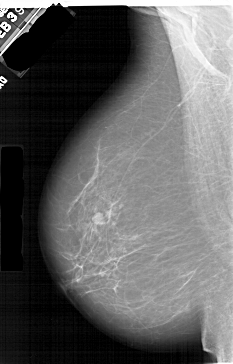

A_1409_1.RIGHT_MLO

RIGHT_MLO LINES 6451 PIXELS_PER_LINE 3736 BITS_PER_PIXEL 12 RESOLUTION 43.5 OVERLAY